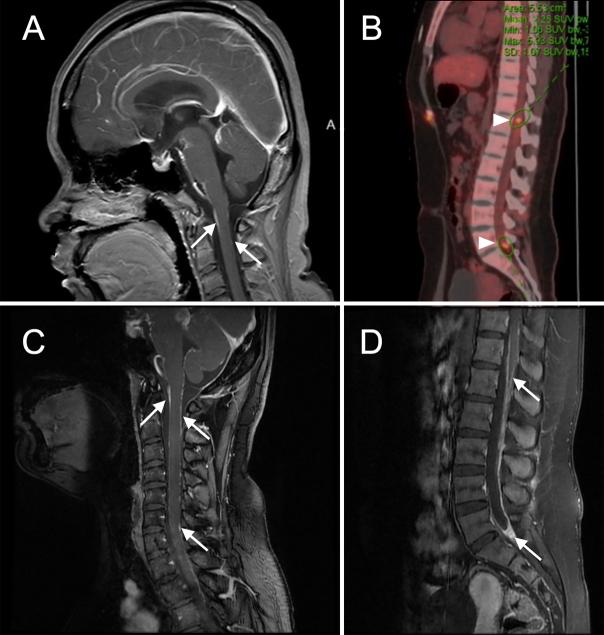

Diffuse leptomeningeal glioneuronal tumor (DLGNT) is a rare central nervous system tumor, especially in adult females. Typically, it presents with leptomeningeal enhancements in the basal cisterns and spinal cord. However, varied radiological and pathological features can complicate the diagnosis, as the present case illustrates.

An adult female presented with severe headache, blurred vision, and cognitive impairment. Elevated intracranial pressure (ICP) was detected via lumbar puncture. Brain magnetic resonance imaging (MRI) revealed atypical unilateral basal cistern enhancement, differing from the usual symmetrical DLGNT presentation. Despite high ICP, only mild ventricular enlargement was observed. Noncontrast spine MRI failed to demonstrate spinal leptomeningeal enhancement. A stereotactic biopsy of an occipital lesion was inconclusive. These atypical findings led to misdiagnoses of viral encephalitis or inflammation at two hospitals. Significant symptom relief occurred only after ventriculoperitoneal (VP) shunt surgery. Over 2.5 years, intraparenchymal lesions in the parahippocampal gyrus grew, necessitating surgical intervention. Pathological examination finally confirmed DLGNT. Postsurgery, the patient underwent chemotherapy with temozolomide and remains symptom free.

弥漫性软脑膜神经胶质瘤(DLGNT)是一种罕见的中枢神经系统肿瘤,在成年女性中尤为少见。通常,它表现为脑基底池和脊髓的软脑膜强化。然而,正如本病例所示,各种不同的放射学和病理学特征会使诊断变得复杂。

一名成年女性出现严重头痛、视力模糊和认知障碍。通过腰椎穿刺检测到颅内压(ICP)升高。脑部磁共振成像(MRI)显示非典型的单侧脑基底池强化,与常见的对称性DLGNT表现不同。尽管颅内压升高,但仅观察到轻度脑室扩大。非增强脊柱MRI未显示脊髓软脑膜强化。对枕部病变进行立体定向活检结果不明确。这些非典型表现导致在两家医院被误诊为病毒性脑炎或炎症。仅在进行脑室腹腔(VP)分流手术后症状才得到明显缓解。在超过2.5年的时间里,海马旁回的脑实质内病变不断增大,需要进行手术干预。病理检查最终确诊为DLGNT。术后,患者接受了替莫唑胺化疗,目前无症状。